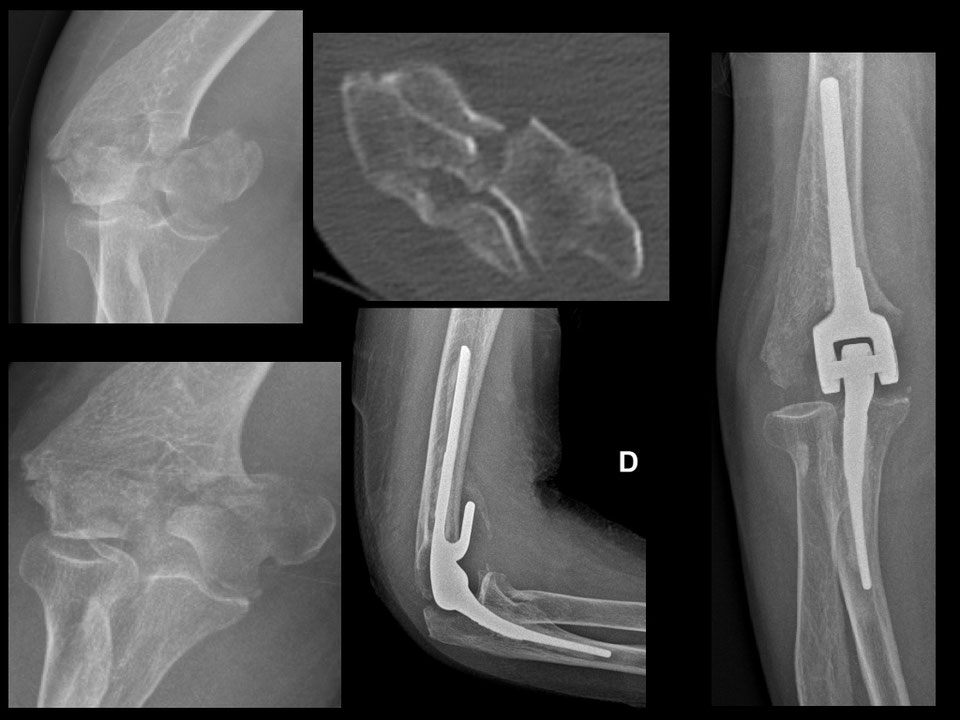

Fractures du COUDE Fractures distales de l humérus Fracture Coude Traitement La fracture du coude désigne le plus souvent la fracture de la parte inférieure de l’humérus, qui est l’os du bras. Le traitement des fractures de l’olécrane repose sur le port d’une attelle, parfois une chirurgie et un traitement par antibiotiques en cas de fracture. Une fracture du coude est une rupture d’un ou plusieurs des os qui constituent l’articulation. Fracture Coude Traitement.